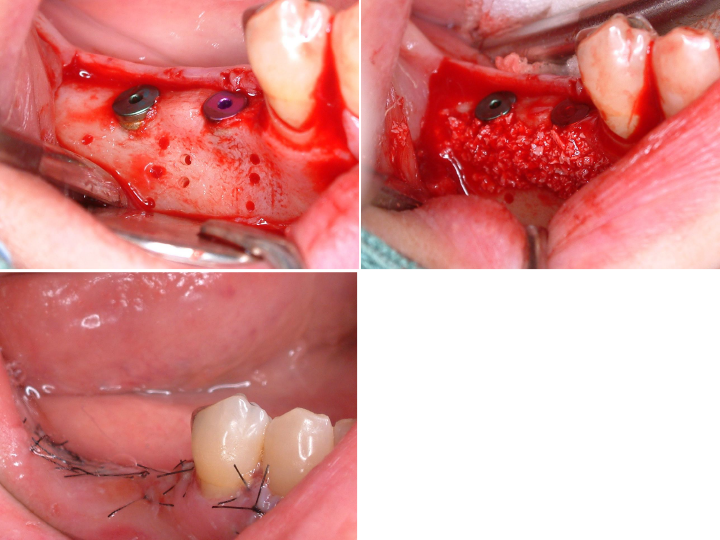

ほぼ骨内には埋入できましたが、骨の厚みが足りないため、人工骨を移植し縫合しました。

埋入後6カ月口腔内写真及びデンタル

インプラントの周囲に固い歯茎(角化歯肉)があるとしっかりと歯ブラシがあてることができます。

インプラントの周囲に固い歯茎を作るために歯茎(角化歯肉)の移植を行いました。